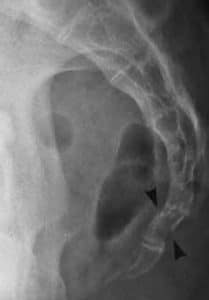

The coccyx (also known as the tailbone) is the terminal part of the vertebral column. It is comprised of four vertebrae, which fuse to produce a triangular shape. In this article, we will discuss the anatomy of the coccyx – its structure, bony landmarks, ligaments and clinical relevance. Pro Feature - 3D Model You've Discovered a Pro Feature Access our 3D Model Library Explore, cut, dissect, annotate and manipulate our 3D models to visualise anatomy in a dynamic, interactive way. Learn More Development and Structure The coccyx arises embryologically as the skeletal remnant of the caudal eminence that is present from weeks 4-8 of gestation. This eminence subsequently regresses, but the coccyx remains. Initially, the four coccygeal vertebrae are separate, but throughout life they fuse together to form one continuous bone. There is considerable variation in structure between individuals. One common variant is failure of the first coccygeal vertebra (Co1) to fuse, remaining separate throughout adult life. In some individuals, there can be one more or one less coccygeal vertebra, giving the individual a coccyx with 5 or 3 vertebrae respectively. Bony Landmarks The coccyx consists of an apex, base, anterior surface, posterior surface and two lateral surfaces. The base is located most superiorly, and contains a facet for articulation with the sacrum. The apex is situated inferiorly, at the terminus of the vertebral column. The lateral surfaces of the coccyx are marked by a small transverse process, which projects from Co1. The coccygeal cornua of Co1 are the largest of the small articular processes of the coccygeal vertebrae. They project upwards to articulate with the sacral cornua. By TeachMeSeries Ltd (2025) Fig 1Bony landmarks of the coccyx. Joints The coccyx articulates with the sacrum at a fibrocartilaginous joint called the sacrococcygeal symphysis. Movement here is limited to minor flexion and extension which occurs passively, for example during defecation and labour. Ligaments The sacrococcygeal symphysis is supported by five ligaments: Anterior sacrococcygeal ligament – a continuation of the anterior longitudinal ligament of the spine, and so connects the anterior aspects of the vertebral bodies. Deep posterior sacrococcygeal ligament – connects the posterior side of the 5th sacral body to the dorsal surface of the coccyx. Superficial posterior sacrococcygeal ligament – attaches the median sacral crest to the dorsal surface of the coccyx. Lateral sacrococcygeal ligaments – run from the lateral aspect of the sacrum to the transverse processes of Co1. Interarticular ligaments – stretch from the cornua of the sacrum to the cornua of the coccyx. Attachments One of the key functions of the coccyx is as an attachment point for various structures. The gluteus maximus attaches to the coccyx, as does the levator ani muscle, which is a key component of the pelvic floor. The anococcygeal raphe is a thin, fibrous ligament which runs from the coccyx and helps support the position of the anus. Clinical Relevance Fractured Coccyx An abrupt fall onto the buttocks, for example falling off a chair, can fracture the coccygeal vertebrae. This condition is normally managed with conservative care, although severe fractures may require in-patient treatment. By Nevit Dilmen (Own work) [CC BY-SA 3.0 ], via Wikimedia Commons Fig 2Radiograph of a fractured coccyx (demonstrated by the arrows). Coccydynia Coccydynia refers to a sensation of general discomfort around the coccyx, and has a wide range of causes. Childbirth may be a cause, as the stretching of pelvic floor muscles during labour puts pressure on their attachment to the coccyx, causing pain. Blunt trauma can contribute, as can poor posture when cycling or rowing, leading to irritation of the bone. Normally coccydynia is an acute condition, although if the pain lasts for more than 3 months it is considered chronic, and requires more specialised treatment. Sacrococcygeal Teratoma A sacrococcygeal teratoma is a tumour of the coccyx that is thought to derive from the embryological primitive streak. Mostly they are benign, although 12% of the time they are malignant and life-threatening. They are present in 1/35,000 live births, and so are the most common presenting tumour in newborns. Do you think you’re ready? Take the quiz below Pro Feature - Quiz The Coccyx Question 1 of 3 Submitting... Skip Next Rate question: You scored 0% Skipped: 0/3 1800 More Questions Available Upgrade to TeachMeAnatomy Pro Challenge yourself with over 1800 multiple-choice questions to reinforce learning Learn More Rate This Article